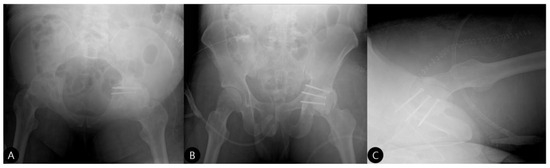

- 15 Months: A CT scan showed a stable joint, concentric reduction, and no signs of screw loosening or osteolysis (Figure 8). The patient reported no functional limitations. The mHHS was 82/100.

- 21 Months: AP pelvic radiographs showed excellent maintenance of joint space and a stable construct without loosening (Figure 9). The patient’s functional outcome was excellent, reporting no pain during daily activities, with only mild discomfort during deep squatting. The mHHS was 85/100.